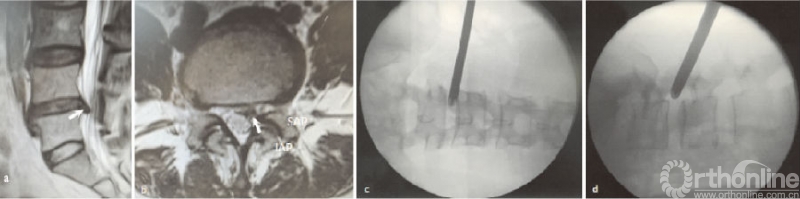

一般除了L5S1节段外,经典的YESS穿刺技术是首选方案,而对于突出位于神经根前方或内侧方向的,可综合测量CT、MR与突出物位置的距离、角度,进行靶点穿刺。在L5S1节段,术前要考虑患者腰骶角、横突、髂骨、椎间盘突出的位置等情况[14],如L5横突粗大造成L5S1横突间距狭窄的,建议行关节突成形或用镜下磨钻来扩大空间,以利于工作通道置入(见图3)。

(a)腰椎正位X线片示左侧横突粗大;(b)穿刺点距离及穿刺方向规划图;(c)(d)工作通道放置X线透视图;○指狭小的工作通道空间

图3 L5S1节段左侧极外侧突出穿刺点及置管图